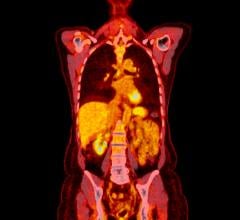

Two abnormal structures called plaques and tangles are prime suspects in damaging and killing nerve cells in Alzheimer's. The plaques are deposits of a protein fragment called amyloid-beta that build up in the spaces between nerve cells. Amyloid PET imaging represents a potential major advance in the clinical assessment of people with cognitive impairment. The technology makes amyloid plaques light up on a brain PET scan, enabling for the first time accurate detection of plaques in living people.

Amyloid PET imaging alone does not establish a diagnosis of Alzheimer's disease, but must be considered in the context of the person's medical history, physical examination and cognitive testing. To guide clinicians on how best to apply amyloid PET in the clinical evaluation of people with cognitive decline, a working group convened by the Alzheimer's Association and the Society of Nuclear Medicine and Molecular Imaging (SNMMI) developed appropriate use criteria (AUC) for brain amyloid PET scans.

The AUC indicate that amyloid PET should only be considered in patients with clear, measurable cognitive deficits when there is substantial diagnostic uncertainty after a comprehensive evaluation by a dementia specialist. According to AUC, amyloid PET may have greatest value in patients with either: (1) progressive, unexplained mild cognitive impairment (MCI); or (2) dementia of uncertain cause due to atypical or mixed symptoms, or unusually early age-of-onset.